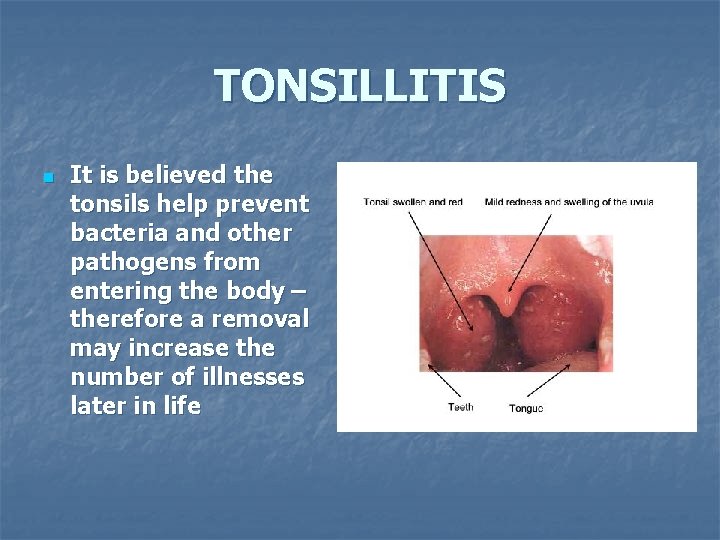

TONSILLITIS n It is believed the tonsils help prevent bacteria and other pathogens from entering the body – therefore a removal may increase the number of illnesses later in life